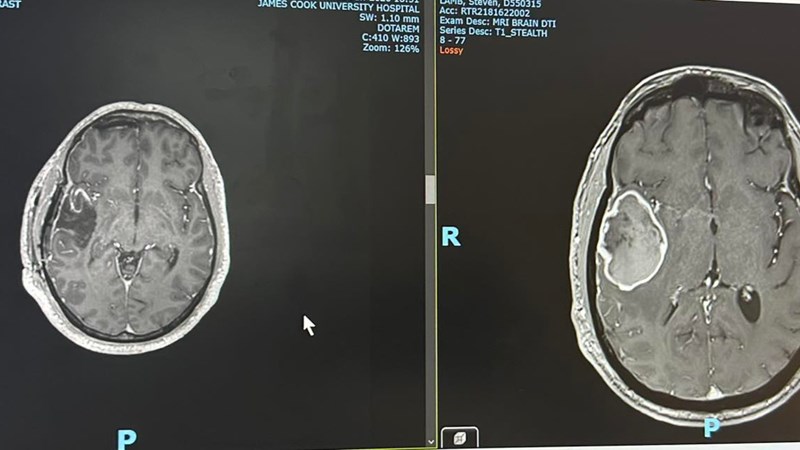

In December 2025, after weeks of severe headaches and a sudden seizure, a scan revealed a 4cm tumour in my right temporal lobe. Two craniotomies removed 98–99% of it, but the diagnosis was confirmed: Grade 4 Glioblastoma wild type un-methylated.